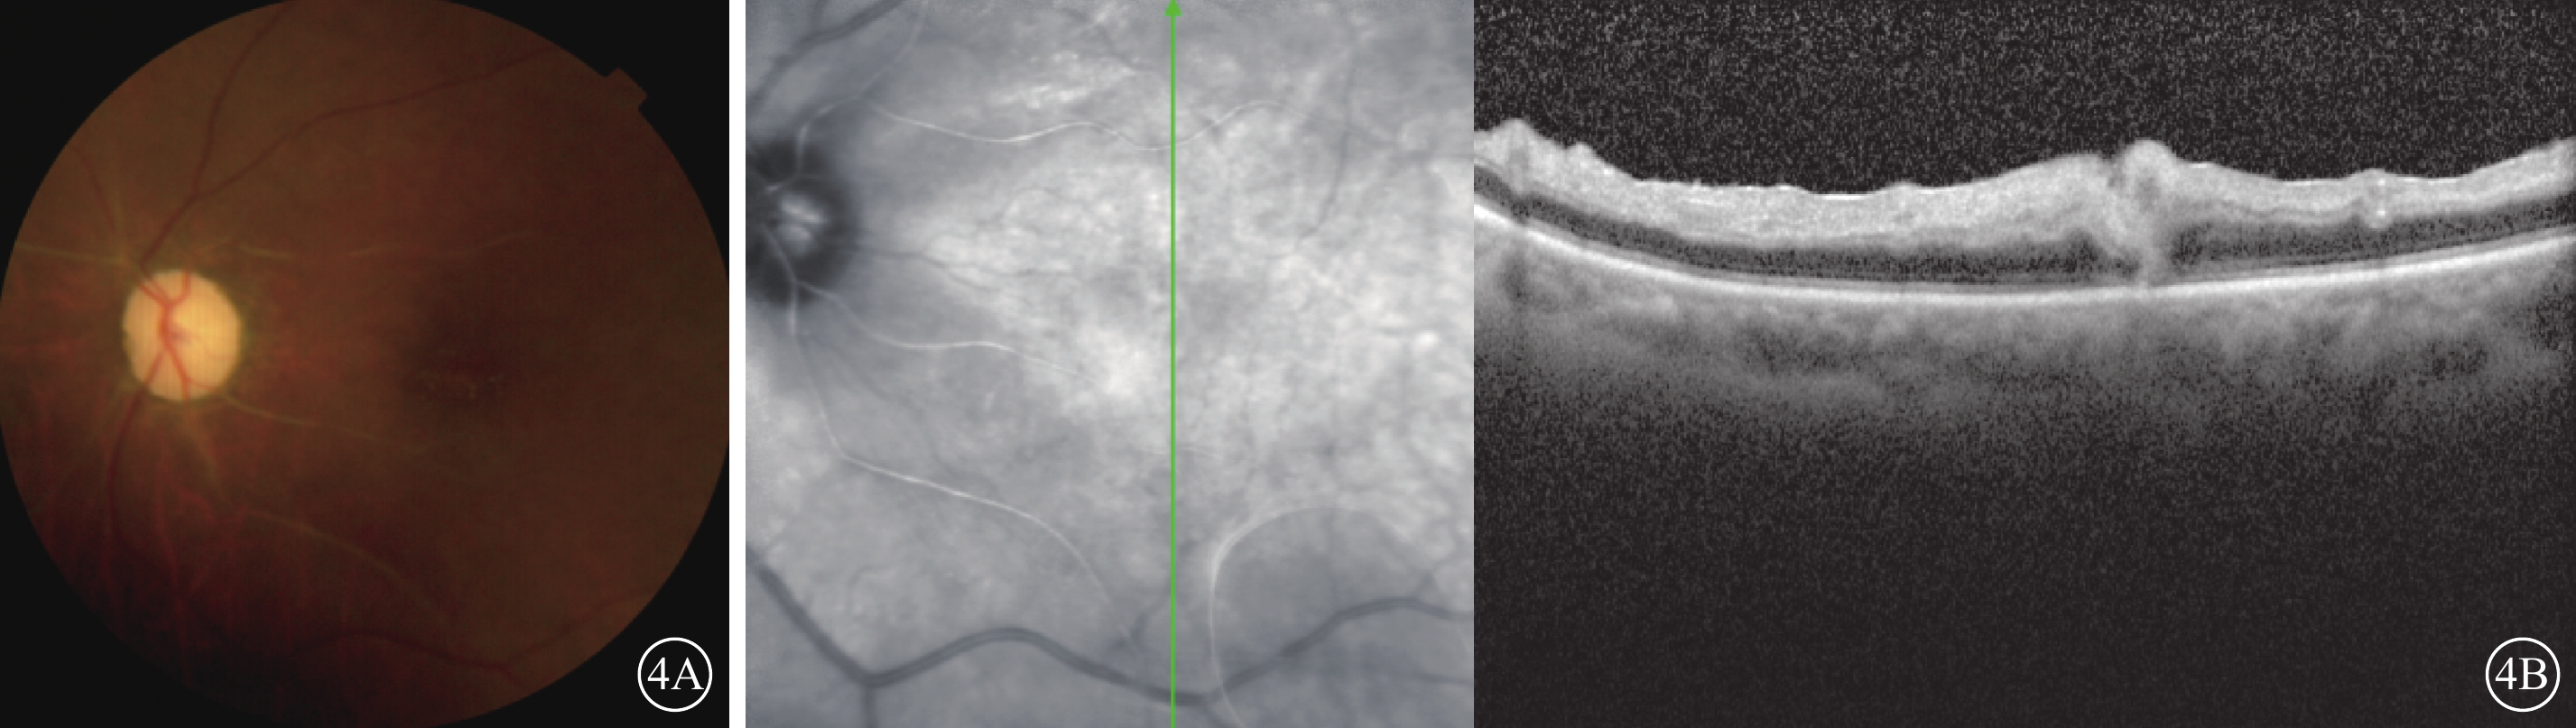

治療:手術后第2天因左眼黑矇,立即給予硝酸甘油500 μg舌下含服,吸氧,球后注射罌粟堿30 mg,同時全身擴容、擴血管、降眼壓、抗凝、神經營養及甲基強的松龍沖擊等治療。手術后第4天,患者自覺左眼視物發黑轉為發紅,但視力檢查仍無改善。手術后第35天復診,眼底視盤邊界清楚,顏色蒼白;視網膜水腫減輕,黃斑高度隆起減輕,視盤鼻側羽毛狀灰白色病灶轉淡,部分視網膜血管呈白線狀(圖4A)。OCT檢查,視網膜內層水腫減輕,層次仍不清晰,黃斑中心凹處橢圓體帶無恢復(圖4B)。

左眼手術后第35天彩色眼底、OCT像。4A示彩色眼底像,視盤顏色蒼白,鼻側羽毛狀灰白色病灶轉淡;視網膜水腫減輕,部分視網膜血管呈白線狀。4B示OCT像,左圖為掃描部位和方向,右圖為檢查結果。黃斑區視網膜內層水腫減輕,但層次仍不清晰,黃斑中心凹處橢圓體帶無恢復

左眼手術后第35天彩色眼底、OCT像。4A示彩色眼底像,視盤顏色蒼白,鼻側羽毛狀灰白色病灶轉淡;視網膜水腫減輕,部分視網膜血管呈白線狀。4B示OCT像,左圖為掃描部位和方向,右圖為檢查結果。黃斑區視網膜內層水腫減輕,但層次仍不清晰,黃斑中心凹處橢圓體帶無恢復

治療:手術后第2天因左眼黑矇,立即給予硝酸甘油500 μg舌下含服,吸氧,球后注射罌粟堿30 mg,同時全身擴容、擴血管、降眼壓、抗凝、神經營養及甲基強的松龍沖擊等治療。手術后第4天,患者自覺左眼視物發黑轉為發紅,但視力檢查仍無改善。手術后第35天復診,眼底視盤邊界清楚,顏色蒼白;視網膜水腫減輕,黃斑高度隆起減輕,視盤鼻側羽毛狀灰白色病灶轉淡,部分視網膜血管呈白線狀(圖4A)。OCT檢查,視網膜內層水腫減輕,層次仍不清晰,黃斑中心凹處橢圓體帶無恢復(圖4B)。

圖4

左眼手術后第35天彩色眼底、OCT像。4A示彩色眼底像,視盤顏色蒼白,鼻側羽毛狀灰白色病灶轉淡;視網膜水腫減輕,部分視網膜血管呈白線狀。4B示OCT像,左圖為掃描部位和方向,右圖為檢查結果。黃斑區視網膜內層水腫減輕,但層次仍不清晰,黃斑中心凹處橢圓體帶無恢復

圖4

左眼手術后第35天彩色眼底、OCT像。4A示彩色眼底像,視盤顏色蒼白,鼻側羽毛狀灰白色病灶轉淡;視網膜水腫減輕,部分視網膜血管呈白線狀。4B示OCT像,左圖為掃描部位和方向,右圖為檢查結果。黃斑區視網膜內層水腫減輕,但層次仍不清晰,黃斑中心凹處橢圓體帶無恢復